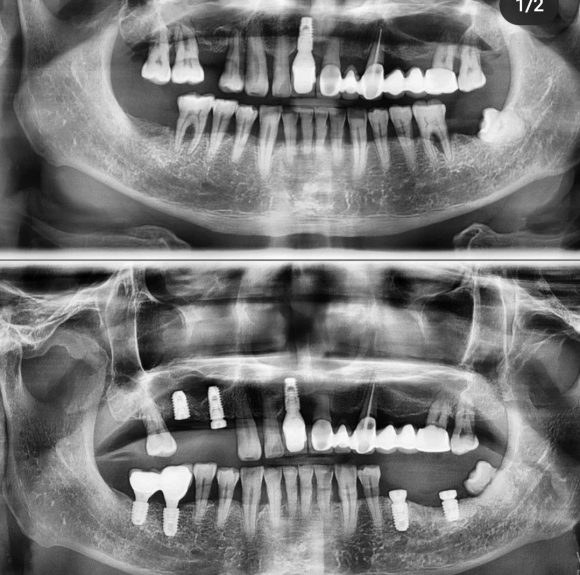

2022.3.30 #35, 37 implant 수술. 양쪽 임플란트 완성되어가는 중. #37은 신경손상 방지를 위해 매우 보존적으로!

저희 숭실대 입구역 리더스진 치과는 한달 평균 임플란트 60~100개를 꼼수 없이 가장 좋은 재료와 기술로 원칙적으로 식립하는 치과입니다.